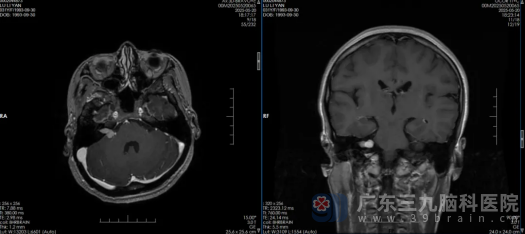

我院神经外十科欧阳辉教授接诊了患者。进一步头颅MRI提示:右侧桥小脑角区占位性病变,考虑听神经鞘瘤;三叉神经薄层扫描TOF序列显示:右侧三叉神经颅内段根部内侧一小血管穿行,关系密切。请结合临床。结合患者的病史,初步诊断为右侧桥小脑角听神经瘤,右侧继发性三叉神经痛。